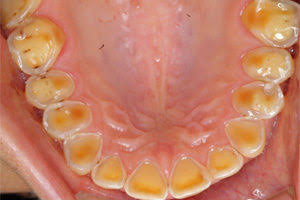

みなさん酸蝕歯と聞いてもよく分からない方が多いかと思いますがその名の通り酸によって蝕まれた歯のことを言います!

などなどが原因によりphの値が5.5以下になってしまうと写真のような状態を招いていきます!

↑こちらは酸によって歯が溶けて薄くなり歯の中の象牙質という所が見えてきている状態です!